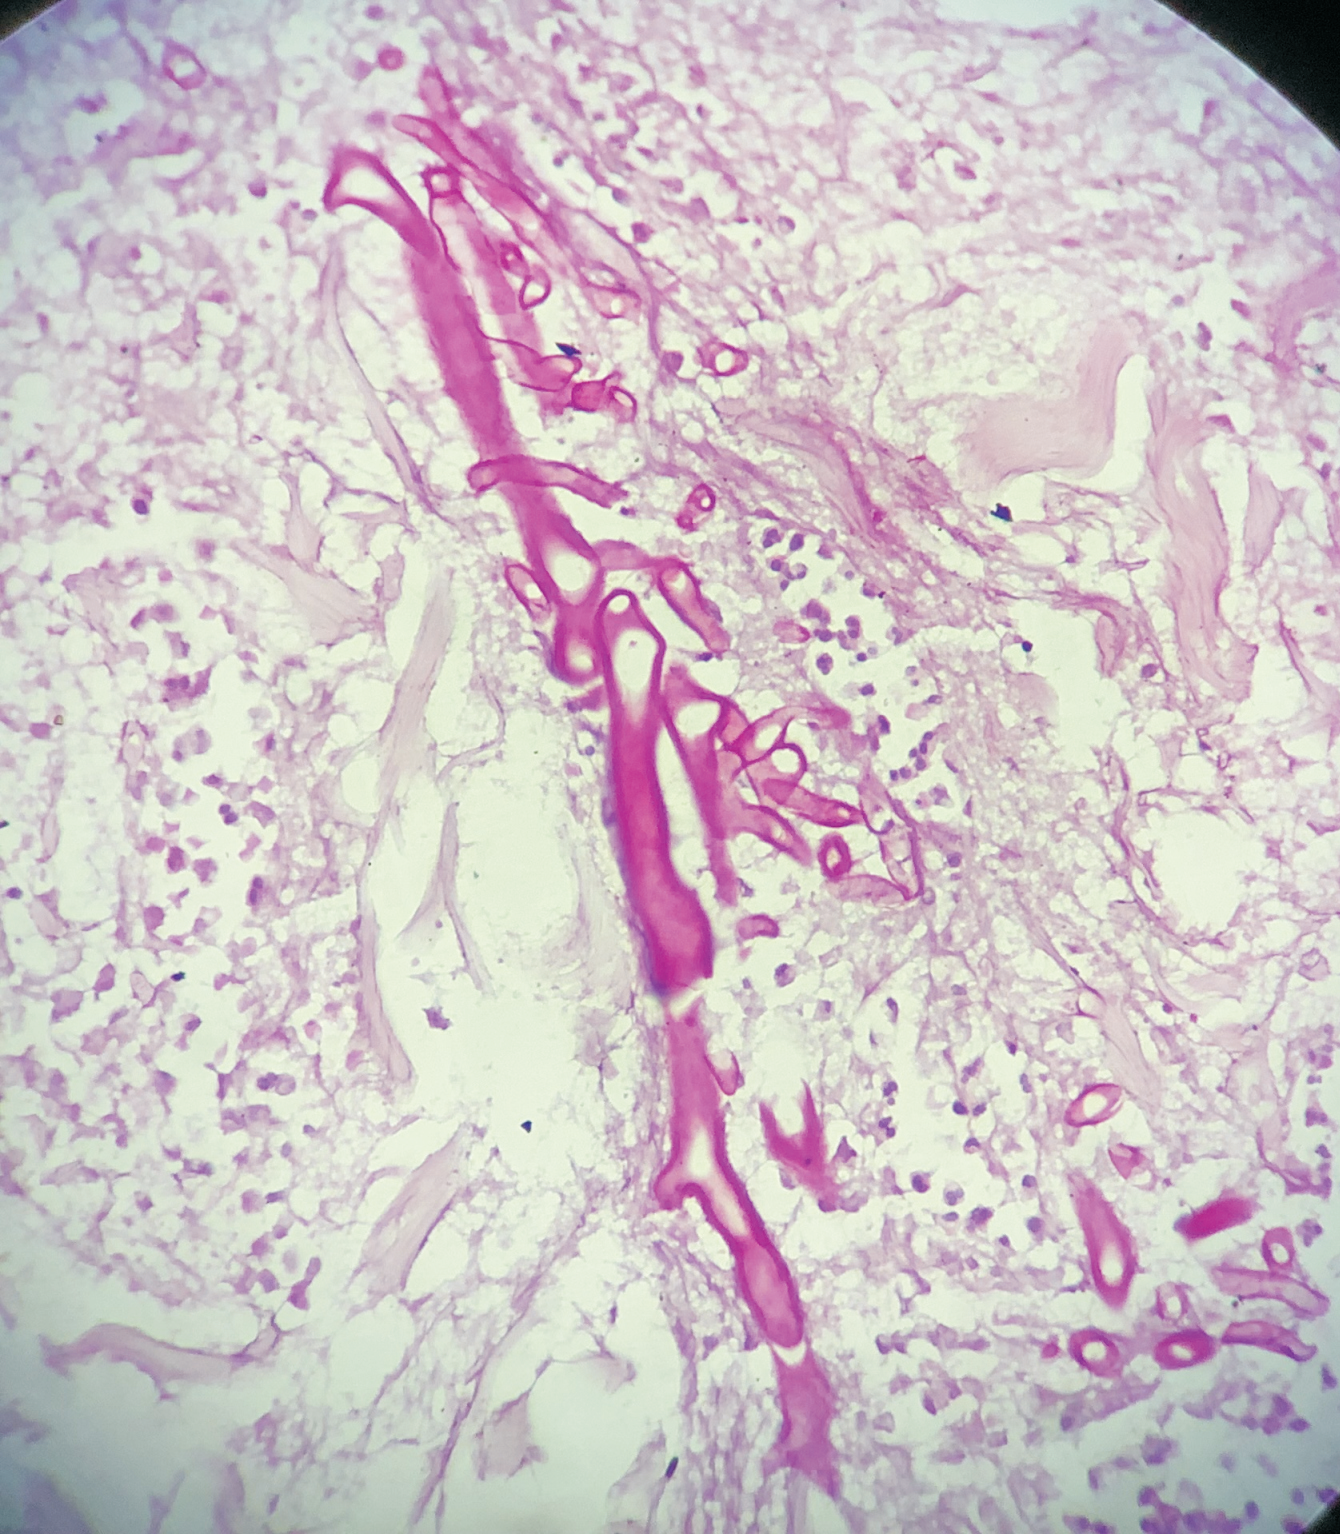

A 76-year-old female presented with multiple fluid-filled painful skin lesions all over the body for the past three months. The patient was normal for three months, later she developed multiple red raised itchy lesions over her hands followed by development on the chest. These lesions progressively increased in number and progressed to the whole body sparing the oral mucosa, genitals, palms, soles and scalp. This fluid-filled lesion did not rapture on pressure and tended to heal. The lesions were associated with pain, acute in onset, penetrating type with a moderate intensity which was relieved on taking medications. No history of pus discharge from these lesions neither there was any history of drug intake. She did not have any history of allergens. She was a known case of Diabetes Mellitus and hypertension. ECG was done which was suggestive of inferior wall ischemic changes for which cardiology reference was done after which 2D ECHO was done which was suggestive of CAD with concentric LVH with normal LVEF(56%) and mild MR. The patient was suggestive for CAG but she refused hence conservative management was done. On Examination Nikolsky's sign was negative while the bullae spread sign could not be elicited. A biopsy of the lesion was done which on histopathology revealed a subepidermal blister with eosinophilic-rich infiltrates in the papillary dermis. She was diagnosed with bullous pemphigoid and was treated with corticosteroids, antibiotics and topical ointments. On Post-treatment head to toe examination, there was a necrotic skin patch of about 4x4 cm over the right scapular region with a line of demarcation, with healthy surrounding skin with no active bleed or pus discharge (Figure 1). Surgery consultation was done and necrotic tissue was excised and sent for histopathological examination. Gross examination showed a fibro-fatty skin-covered tissue piece measuring 8.5 x 4.5 x 2.0 cm. The skin surface was necrosed. The cut surface was grey-brown to grey-yellow. When the microscopic examination was done sections showed ulcerated skin surface with necroinflammatory exudates viable epidermal lining or skin adnexa noted. Underneath the ulcerated surface, there was predominantly necrotic tissue, dense fibrin-inflammatory exudates, foci of fat necrosis, hhemorrhage, and congested to thrombosed blood vessels. Also noted are many scattered broad non-branched aseptate fungal hyphae infiltrating into fibro-fatty tissue collagenous septae and occasional vessels as well (Figure 2). PAS and GMS stain highlighted aseptate broad fungal hyphae confirming mucormycosis (Figure 3,4). Thus a final diagnosis of Invasive Mucormycosis with extensive necrosis was made. The patient was treated with anti-fungal drugs (Amphotericin B) and was kept on follow-up. After one month she succumbed to death due to coronary heart disease leading to heart failure.

![Photo micrograph showing multiple broad non-branched aseptate fungal hyphae [H&E, 400X]](https://s3-us-west-2.amazonaws.com/typeset-prod-media-server/c5743307-b164-4e88-a493-3f03bf7131d0image2.png)